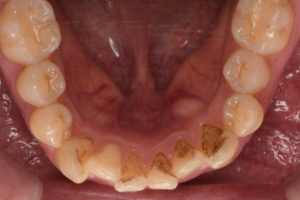

CASE 10

Before①

After①

Before②

After②

基本情報

| 年齢・性別 | 38歳・男性 |

| 主訴 | 下顎 歯石除去したい |

| 治療内容 | スケーリング |

| 治療期間 | 30分 |

| 治療費 | 約1,500円(保険診療) |

| リスク・副作用 | 知覚過敏、歯肉退縮 |

| 治療方針 | 歯肉縁上歯石を除去してから歯肉縁下歯石を除去します。ご自身でのプラークコントロールができるようになったら定期検診に移行します。 |

| 担当者所見 | 半年ぶりの歯科医院の受診。歯石が付きやすいためセルフケアの重要性をお伝えして、定期的にクリーニングを行います。出血率が高く炎症が強いため、今後はセルフケアを強化して歯周病治療を行います。 |